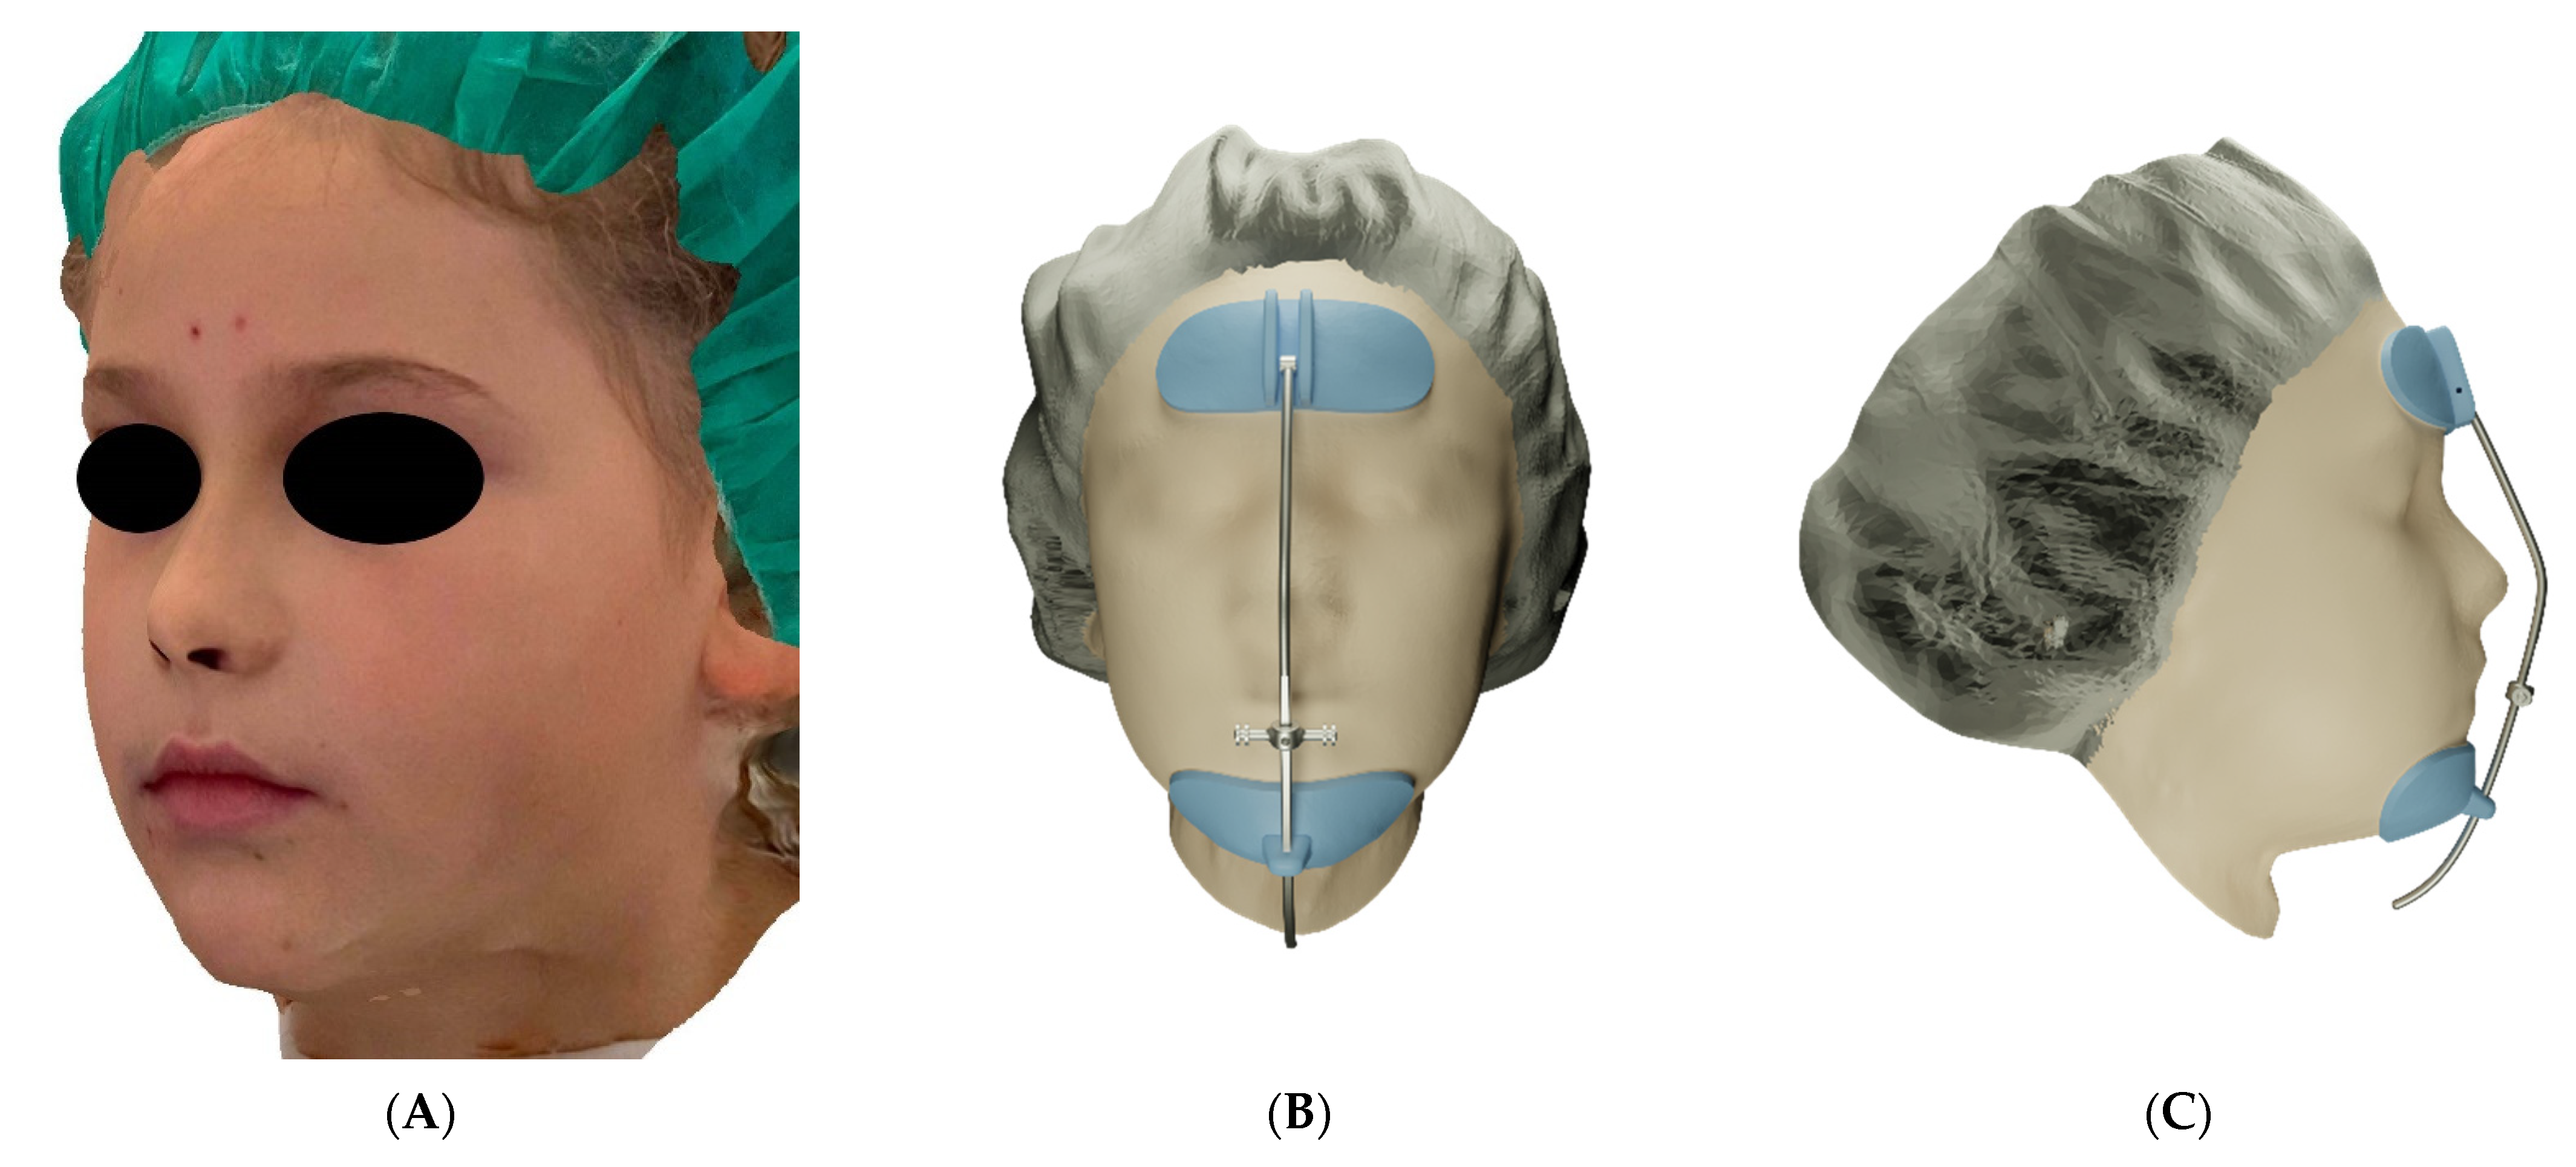

3D Printed Customized Facemask for Maxillary Protraction in the Early Treatment of a Class III Malocclusion: Proof-of-Concept Clinical Case

2. Materials and Methods

3. Results